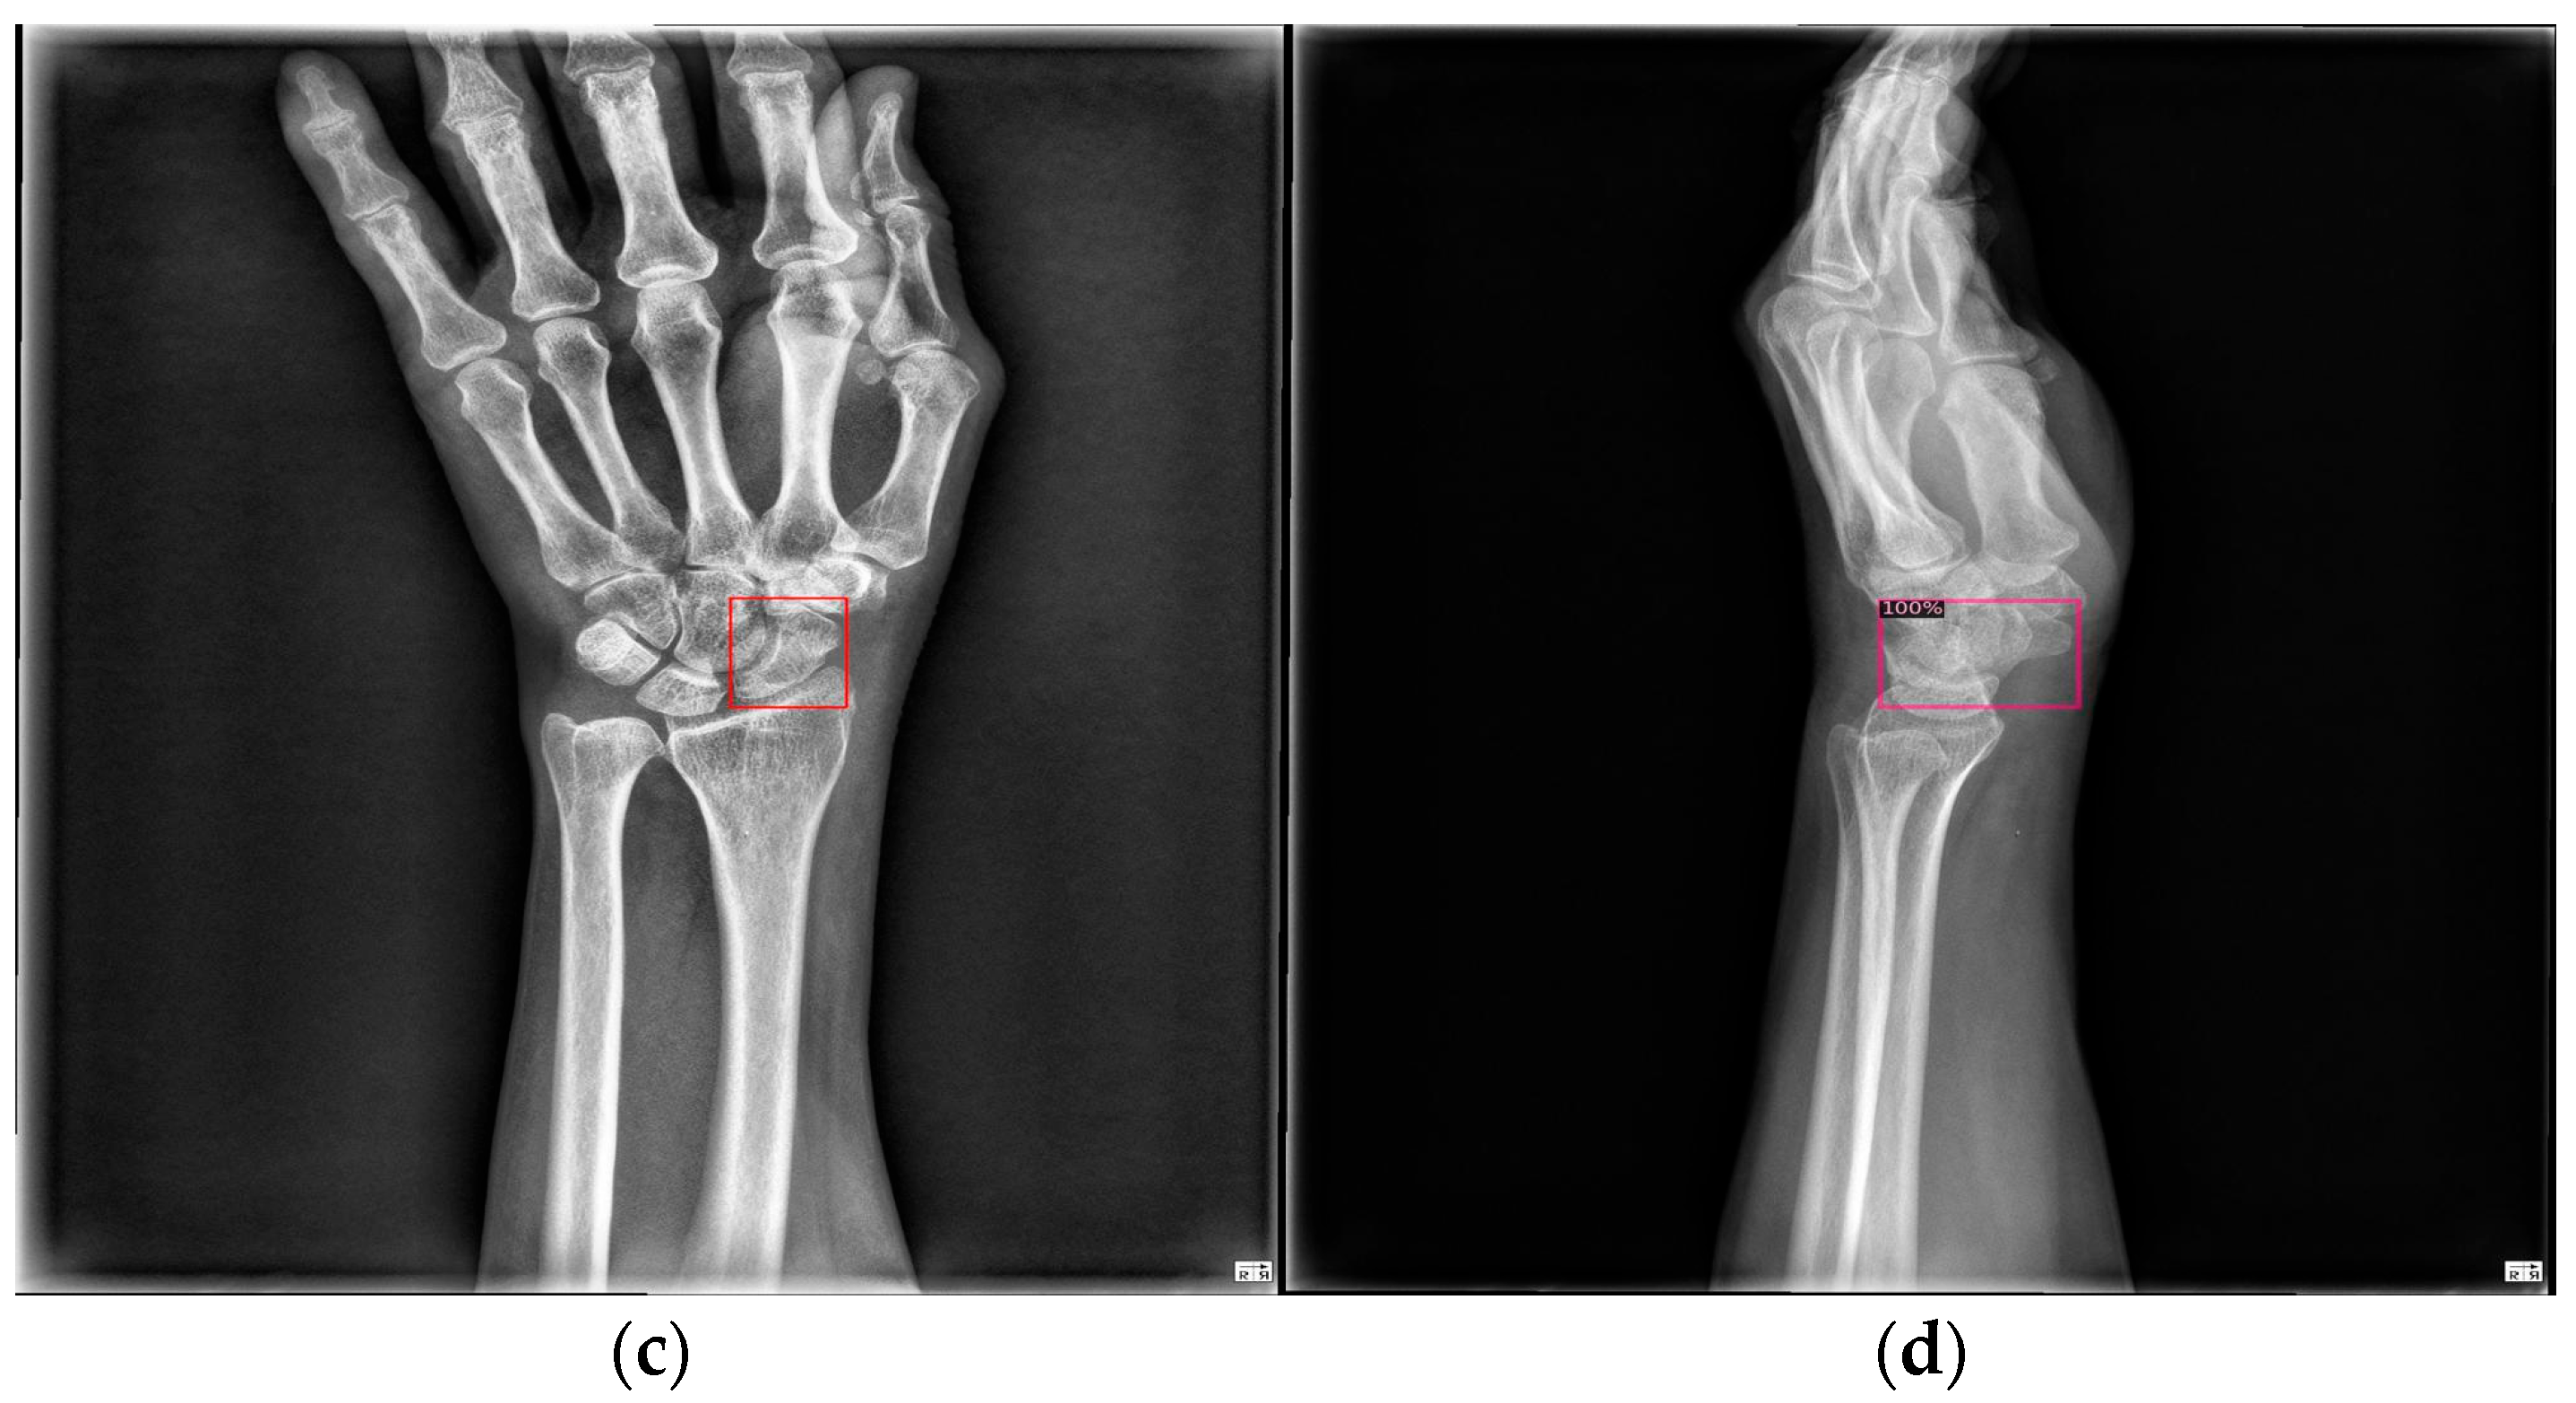

Figure 9 shows the results of scaphoid fracture detection. In the figure, the red area represents the ground-truth box labeled by the doctor, while the green area shows the result predicted by the model. Figure 10 provides an example of a more obvious fracture, whereas Figure 11 illustrates an example of an occult fracture. These examples highlight the challenges in diagnosing scaphoid fractures, as occult fractures are difficult to distinguish by the naked eye. The AP views demonstrate a relatively high IoU, while the LA views also accurately locate the fracture area. This combined approach is effective in drawing the doctor’s attention to the area, enabling quicker identification of the fracture location.

Figure 9. Scaphoid detection visualization. (ad) The AP and LA views of the same patient. The first row is the ground truth, and the second row is the predicted result.

Figure 10. Fracture detection visualization. (a,b) Scaphoid bone slices. The red box is the true answer, and the green box is the predicted result.